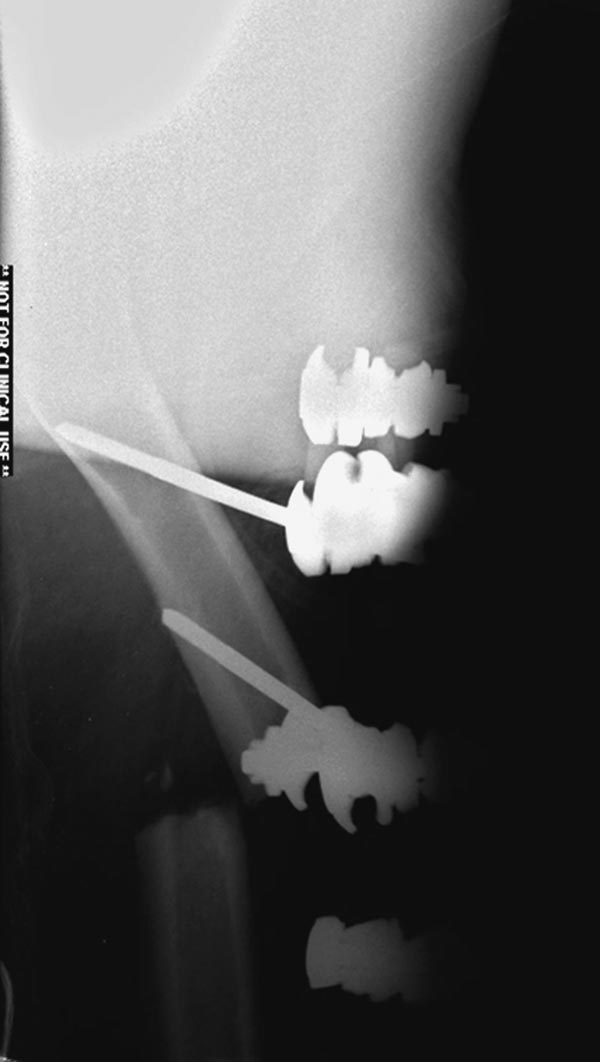

Здесь перечислены ортопедические повреждения: Rt. femoral shaft fracture, Rt femoral head fracture-dislocation, Rt distal femur fracture, Rt. open patella fracture, Rt. talus fracture dislocation, Rt. open humerus fracture, Left 5th metatarsal fracture, Left dislocation 1st TMT.

6 день госпитализации-операция на таранной кости.